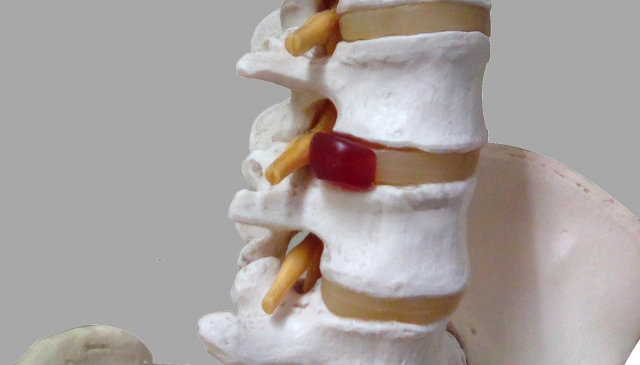

ヘルニアとは椎間板が飛び出したものを言います。椎骨と椎骨の間には「椎間板」というクッションがあります。この椎間板が生活習慣や外的要因によって衝撃を受け変形をきたし飛び出したものを椎間板ヘルニアといい、神経を圧迫して痛みやしびれなどの症状を起こすのを「腰椎椎間板ヘルニア」といいます。

椎間板ヘルニアが起こるのは2通りあります。外的要因(激しいスポーツ・重いものを持った時)によって起こるのと、中腰の姿勢や長時間のデスクワークなどによってヘルニアが生じます。